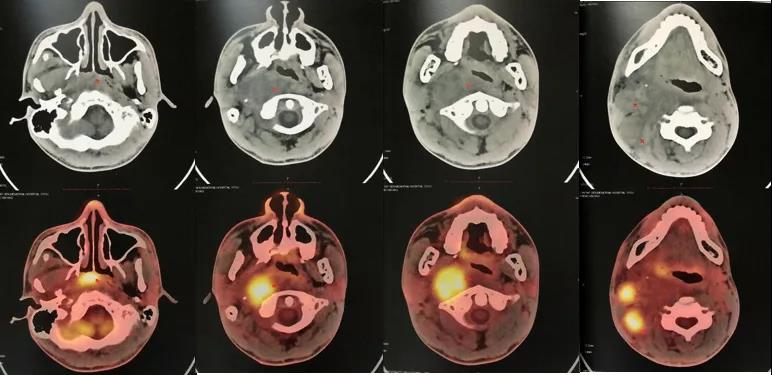

卡瑞利珠单抗联合安罗替尼治疗鼻咽癌1例林建光 康艺苹 许天文 ( 福建医科大学 附属第二医院)01 病例简介患者,女性,34岁。2017年5月于福建医科大学附...